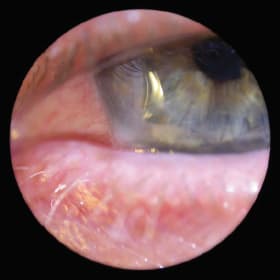

Figure 1. Calcium-like deposition at apex of cornea of a keratoconus patient who suffered from recurrent corneal erosions and was fit with a soft lens under an existing GP lens.